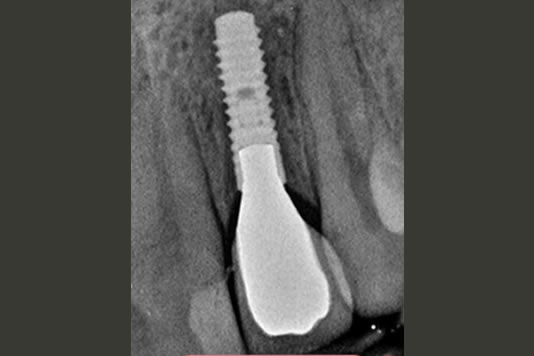

Dental implants are the best-known treatment to replace single or multiple missing teeth because they feel and behave just like natural teeth. After a while you won’t be able to tell the difference – even forgetting that they are there.

The procedure to place implants and replace a missing tooth or multiple teeth is straightforward as there is little need to treat surrounding teeth. Once a crown is placed over the implant it will appear indistinguishable from the natural teeth.